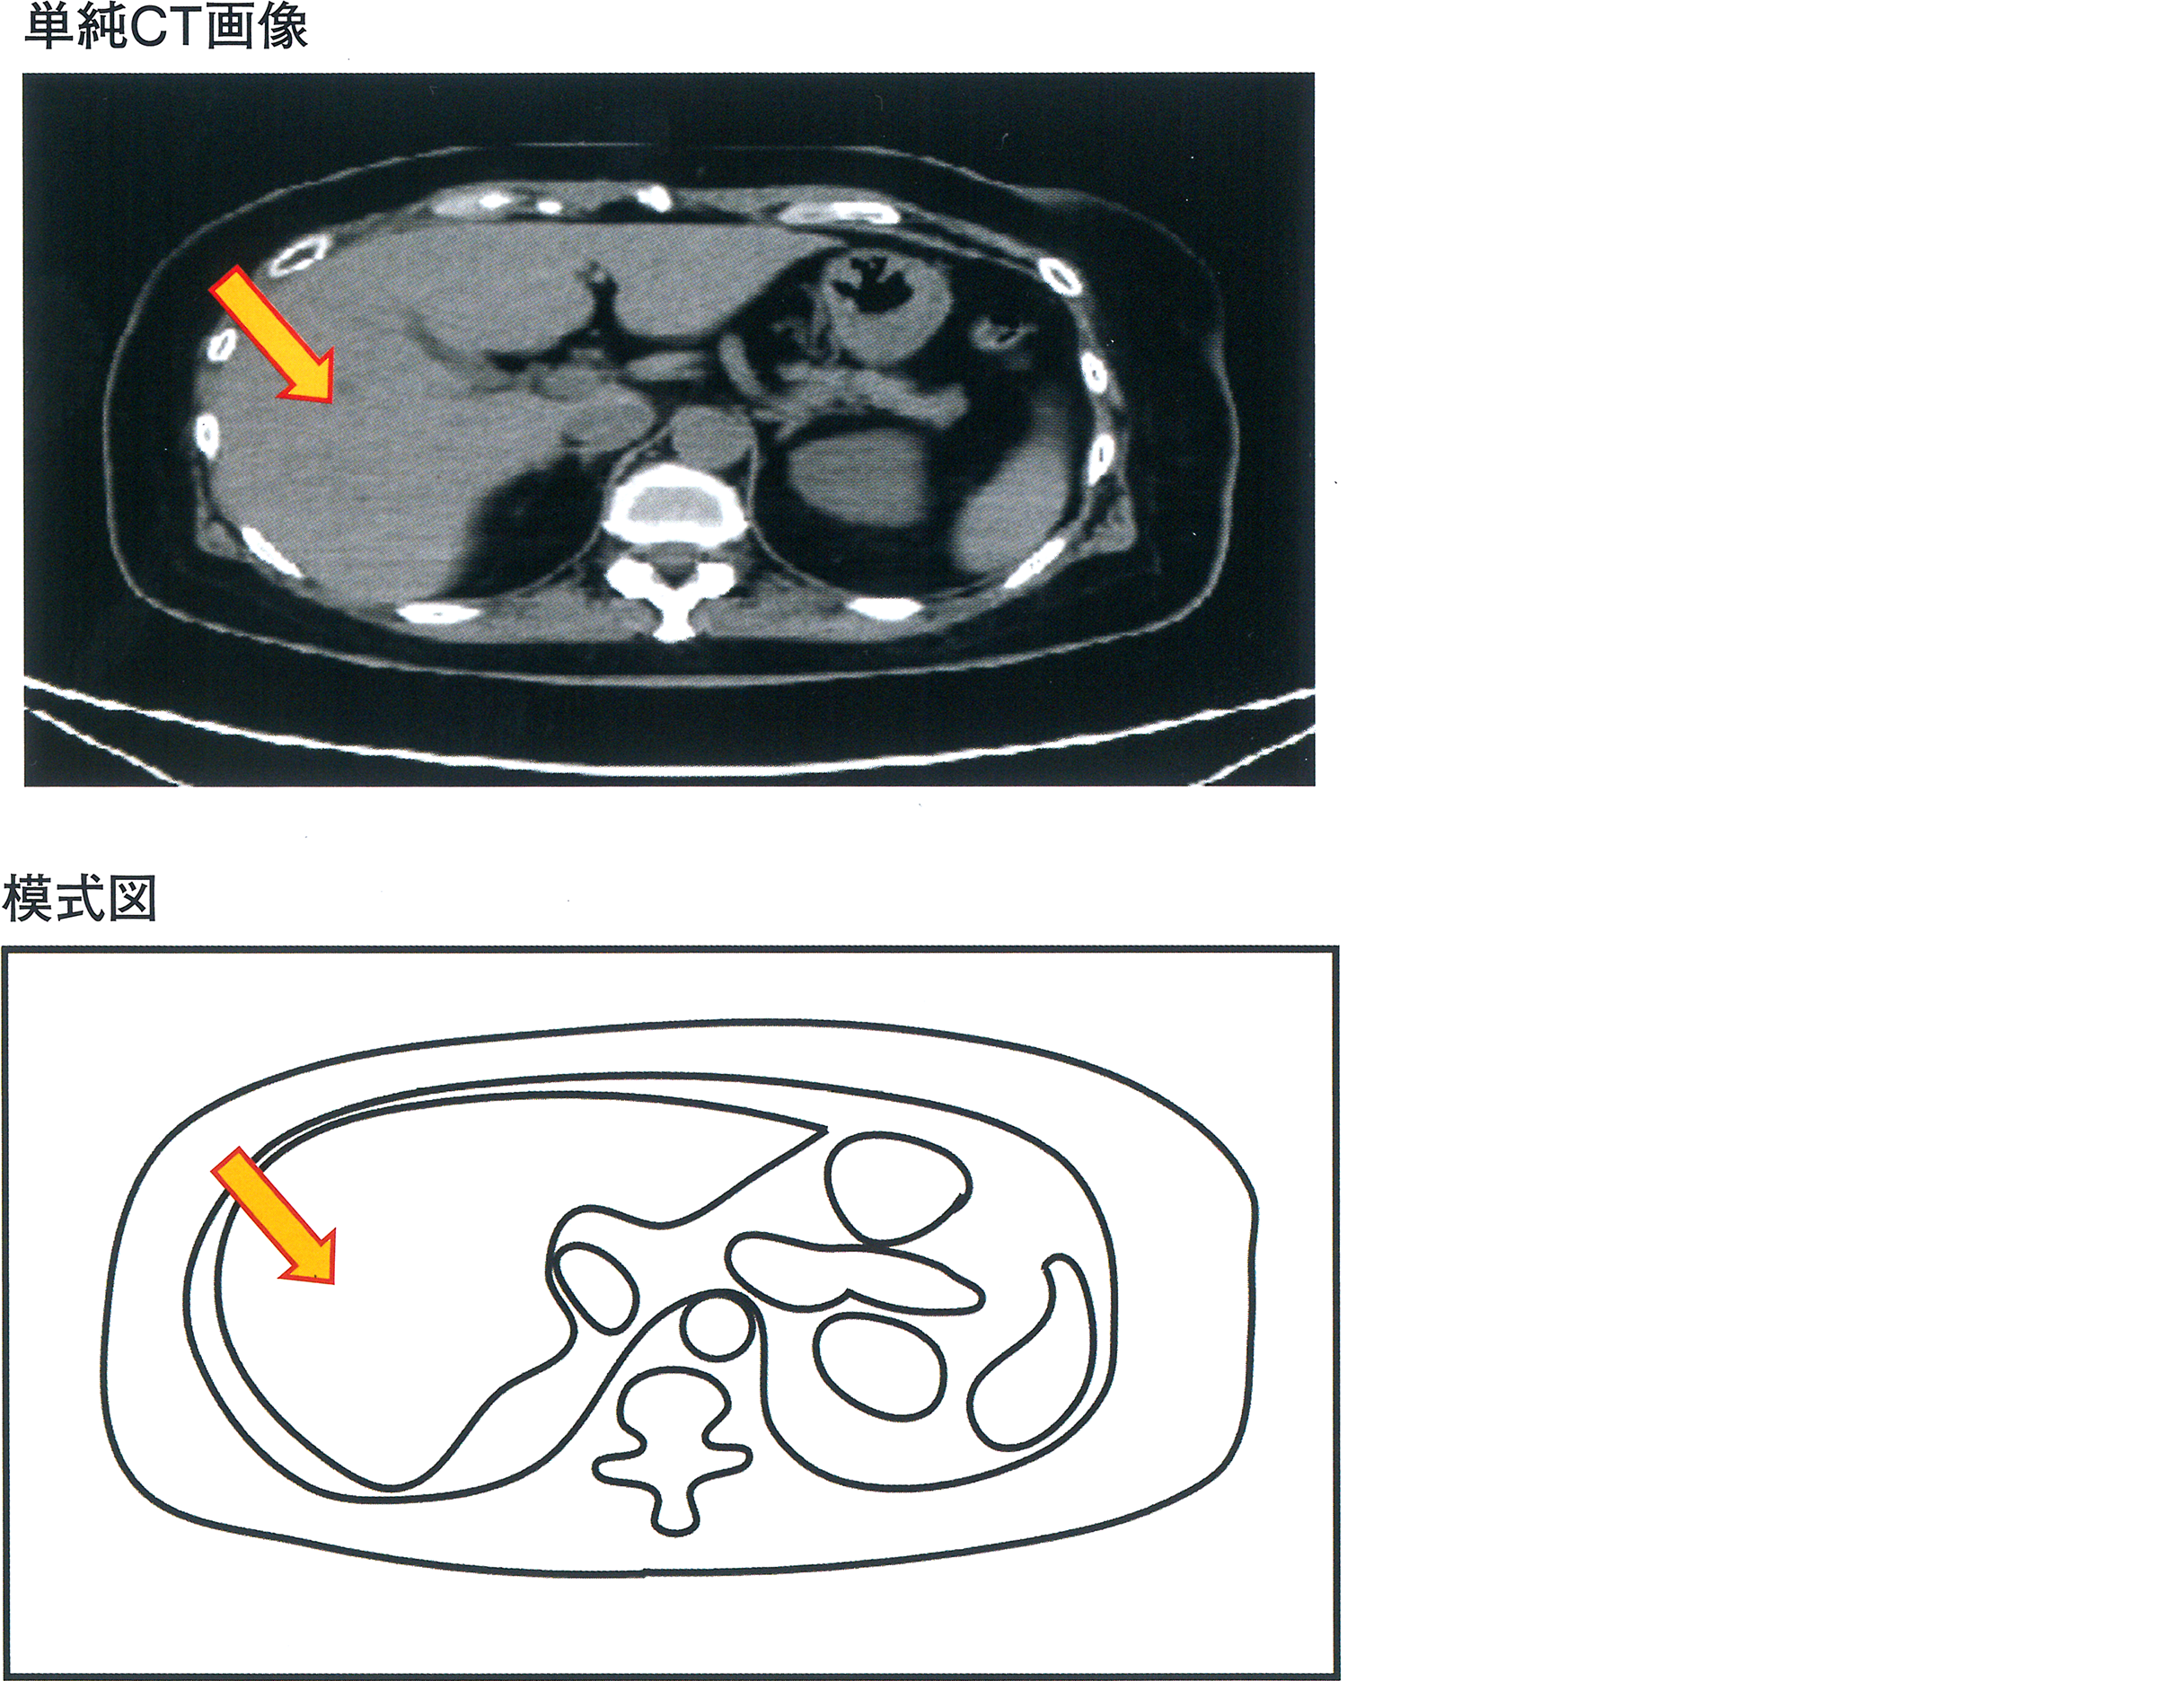

上腹部の単純CT画像(第12胸椎の高さの横断面)とその模式図を示す。

矢印で示す臓器はどれか。

1. 胃

2. 肝 臓

3. 心 臓

4. 脾 臓

5. 大動脈